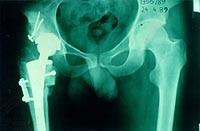

TRATAMIENTO QUIRÚRGICO  Artrodesis de cadera  Osteotomía de cadera  Artroplastias – por reseccion – por interposicion – por sustitucion parcial – por sustitucion total